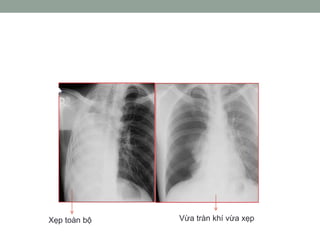

Xquang:

• Có thể thấy hình ảnh xẹp phổi trong tắc hoàn toàn.

• Nếu tắc không hoàn toàn, không khí vào nhưng không ra

được, nên sẽ có tình trạng ứ khí.

Xẹp toàn bộ Vừa tràn khí vừa xẹp

TẮC NGHẼN HÔHẤP DƢỚI Xquang: • Có thể thấy hình ảnh xẹp phổi trong tắc hoàn toàn. • Nếu tắc không hoàn toàn, không khí vào nhưng không ra được, nên sẽ có tình trạng ứ khí.

Xẹp toàn bộVừa tràn khí vừa xẹp